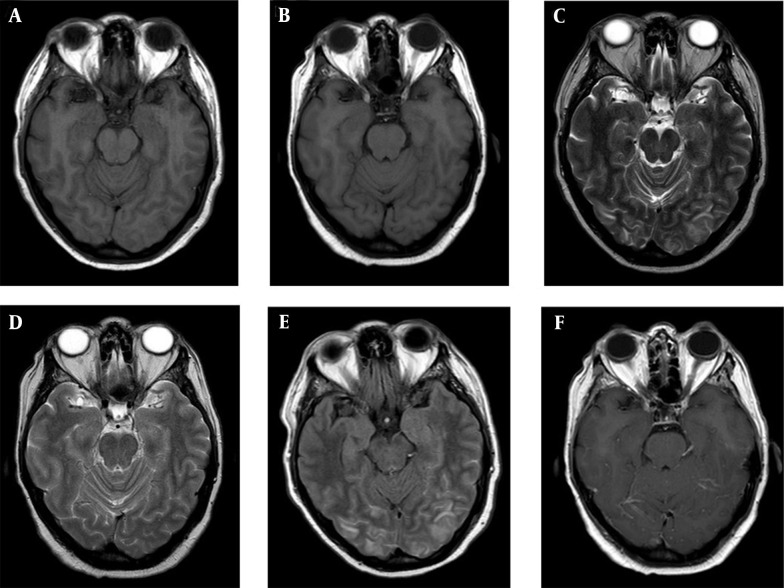

Posterior reversible encephalopathy syndrome (PRES) is an uncommon transient neuroradiological phenomenon that develops vasogenic cerebral edema and could be caused by some pharmacological agents, such as molecular-specific target agents. Lenvatinib belongs to the tyrosine kinase inhibitors and was approved in 2015 for progressive locally advanced or metastatic thyroid cancer refractory to radioactive iodine (I-131) treatment. Herein, we present the case of a 65-year-old woman who, while receiving treatment with lenvatinib for radioiodine-refractory metastatic papillary thyroid carcinoma, developed PRES without hypertension at the initial evaluation. Her clinical and radiological findings improved after withdrawing from the mentioned therapy, and later it was possible to re-incorporate lower doses of the medication, as described in the other three case reports found in the worldwide medical literature. The recognition of this entity is essential to timely suspend the drug and avoid greater comorbidity. This is the first paper reporting this kind of adverse event using lenvatinib in a Hispanic population.